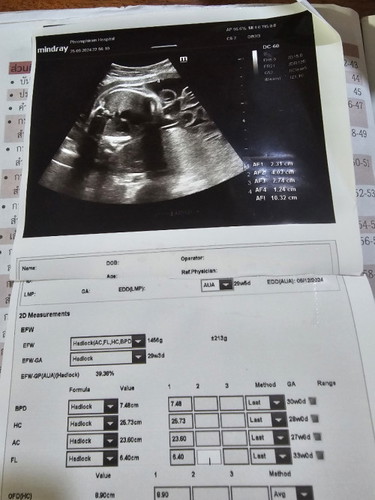

31w น้ำหนัง1200 😊😊😊😊

น้ำหนักลูกน้อย แม่มีอะไรบำรุงน้องบ้างคะ